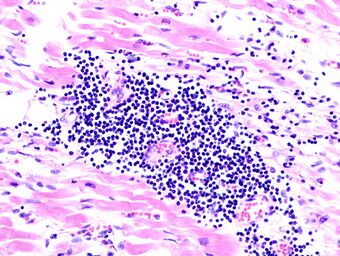

Lymphocytic myocarditis (white arrow points to a lymphocyte), commonly showing myocyte necrosis (black arrow), seen as hypereosinophilic cytoplasm with loss of striations.

The gold standard is the biopsy of the myocardium, in general done in the setting of angiography. A small tissue sample of the endocardium and myocardium is taken and investigated. The cause of the myocarditis can be only identified by a biopsy. Endomyocardial biopsy samples are assessed for histopathology (how the tissue looks like under the microscope): myocardial interstitium may show abundant edema and inflammatory infiltrate, rich in lymphocytes and macrophages. Focal destruction of myocytes explains the myocardial pump failure.[10] In addition samples may be assessed with immunohistochemistry to determine which types of immune cells are involved in the reaction and how they are distributed. Furthermore, PCR and/or RT-PCR may be performed to identify particular viruses. Finally, further diagnostic methods like microRNA assays and gene-expression profile may be performed.[citation needed]